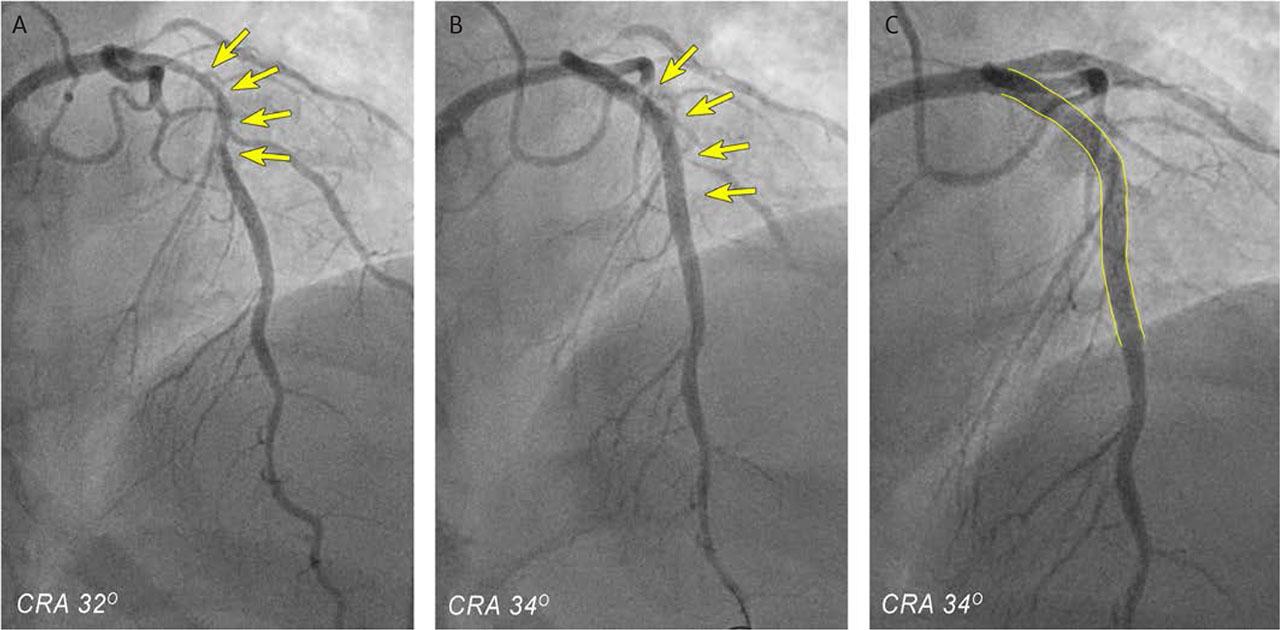

ICA of the target lesion before and after stenting. A. coronary angiography revealing a critical, elongated stenosis in segments I–II of the LAD, characterized by an unstable plaque and overlapping thrombotic material. B,C. Angiographic outcomes after revascularization and stenting of the LAD and IB, showing TIMI 3 flow.

The patient was immediately taken to the cath lab for invasive coronary angiography (ICA). There, a complex 70% stenosis was discovered in the first segment of the LAD. Initially, it was suspected to be a total occlusion but had been partially revascularized during thrombolysis initiated at the secondary department. This long stenosis featured an unstable plaque with overlapping thrombotic material, affecting the first diagonal branch, which is a hemodynamically significant vessel. Additionally, a subocclusive ostial lesion was identified in the intermediate branch (IB), and 30–40% of lesions were found in the right coronary artery (Figure 2A).

The patient then underwent revascularization. During the procedure, a 3 × 33 mm drug-eluting Xience Pro stent (Abbott, Chicago, USA) was implanted in segments I and II of the LAD, extending across the diagonal branch, resulting in a postprocedural TIMI III flow in the LAD. Subsequently, the intermediate branch was stented with a 2.75 × 15 mm drug-eluting Xience Pro stent (Figure 2B).